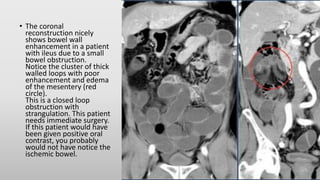

Ileus

• Especially in small bowel obstruction (SBO) ,the most

important question: is there strangulation?

• To answer that question, we need a contrast enhanced

CT for the following reasons:

• A scan at 35 sec p.i. is ideal to show bowel wall

enhancement and possible strangulation.

• Sometimes ischemia can be detected by looking for

differences in enhancement of the bowel wall. This is

best done on coronal thick slabs.

• An obstructing tumor will be better seen.

• Do not use positive oral contrast, because this will

obscure bowel wall enhancement.

• The coronal

reconstruction nicely

shows bowel wall

enhancement in a patient

with ileus due to a small

bowel obstruction.

Notice the cluster of thick

walled loops with poor

enhancement and edema

of the mesentery (red

circle).

This is a closed loop

obstruction with

strangulation. This patient

needs immediate surgery.

If this patient would have

been given positive oral

contrast, you probably

would not have notice the

ischemic bowel.

Ileus • Especially insmall bowel obstruction (SBO) ,the most important question: is there strangulation? • To answer that question, we need a contrast enhanced CT for the following reasons: • A scan at 35 sec p.i. is ideal to show bowel wall enhancement and possible strangulation. • Sometimes ischemia can be detected by looking for differences in enhancement of the bowel wall. This is best done on coronal thick slabs. • An obstructing tumor will be better seen. • Do not use positive oral contrast, because this will obscure bowel wall enhancement.

• The coronal reconstructionnicely shows bowel wall enhancement in a patient with ileus due to a small bowel obstruction. Notice the cluster of thick walled loops with poor enhancement and edema of the mesentery (red circle). This is a closed loop obstruction with strangulation. This patient needs immediate surgery. If this patient would have been given positive oral contrast, you probably would not have notice the ischemic bowel.